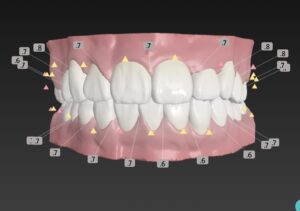

🔶アフター🔶

正面